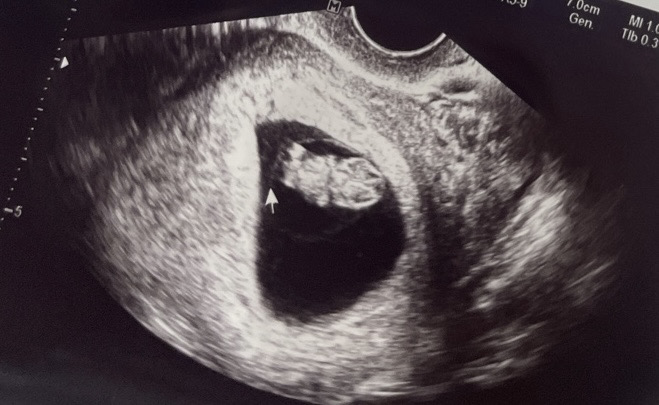

젤리곰 보고왔어요 🪼🧸

보고싶던 팔다리 뾱뾱… 심장 아플 정도로 귀여워요 9주 0일차에 보고왔어요! 자고 있어서 움직이는 건 못 봤지만, 의사 선생님도 이 때가 정말 귀여운 시기라고 하시네요 ☺️ 덕분에 입덧을 좀 더 잘 견딜 수 있게 되었어요 3월생 붉은말띠 예비엄마아빠들, 힘든 시기에 모두 조금만 더 파이팅하세요!